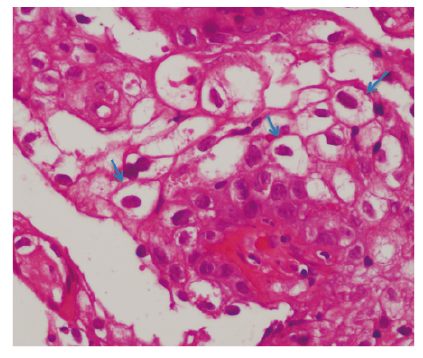

La anatomía patológica informó hallazgos compatibles con lesión papilomatosa y focos sugestivos de infección viral (coilocitos) (Figura 3).